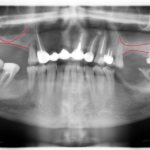

фото: схема аппарата Брюкля

Фото: аппарат Брюкля-Рейхенбаха